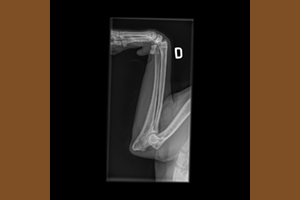

La displasia dell’anca e del gomito è una delle problematiche più conosciute nei cani di taglia grande dove il peso ed il rapido accrescimento evidentemente sono un'aggravante. Vi sono anche altri fattori che possono contribuire ed incidere sulla gravità ma alla base c'è comunque l'ereditarietà (che conta almeno per un 30%), per questo è fondamentale per un allevatore selezionare accuratamente i riproduttori, e per un futuro proprietario selezionare accuratamente l’allevatore, e diffidare da cucciolate improvvisare ove, seppur i cuccioli vengano ceduti con il pedigree, né i genitori né gli avi a monte sono stati controllati ufficialmente.

La displasia non è una patologia congenita, ovvero il cucciolo nasce sano, ma è una patologia dell’accrescimento: una serie di fattori che, agendo progressivamente nel tempo, possono arrivare nei casi più seri al blocco dell'articolazione. Quindi un cucciolo displasico è predisposto geneticamente alla patologia ma alla nascita, così come alla cessione dopo i 60 giorni, non è clinicamente malato; le sue componenti ossee, infatti, sono al momento normali nonostante la predisposizione genetica, che è necessaria per lo sviluppo della patologia. La sintomatologia clinica inizia generalmente dopo i 4 mesi o comunque entro l’anno di età, ma non è raro che la patologia diventi manifesta anche successivamente. Le terapie sono quasi sempre chirurgiche e successivamente fisioterapiche, con costi importanti e con una gestione del cucciolo davvero molto impegnativa e scadente dal punto di vista della socializzazione.